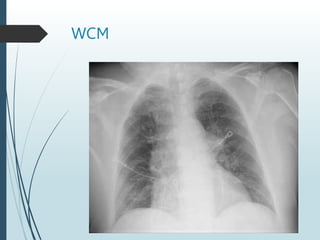

WCM 4/2022

 65 yo presents to OSH with “COPD flare and NSTEMI”

 EMS called nonresponsive, 02 sat 60% Placed on BiPAP

 History COPD since 2017, Flare 1-2 times per year . Not on 02

 At OSH ABG 7.1/88/124 on 02

 Elevated troponins, LFTs, AKI, pBNP 1700, Hgb 18

 CT ruled out PE, No pneumonia

 History of sleep apnea x years but never used machine

 On inhalers for COPD No PFDs

 On transfer hypercarbic and hypoxic respiratory failure.

 Diuresis, on /off bipap, ABX and Steroids

WCM